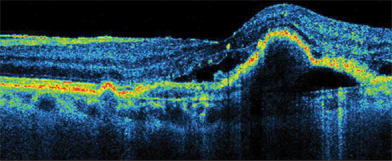

SDOCT does not skip or miss data points, as time domain OCT does because of its speed limitations. Thickness data between time domain scan lines is not actually measured, and values must be interpolated. No interpolation is needed with SDOCT. "We can see pathology that time domain OCT would have missed," Dr. Sharma says. "For example, SDOCT detects drusen or areas of subretinal fluid (Figure 1) that would have fallen between scans on time domain OCT. Also, it is much easier to discriminate pathology with SDOCT technology. For example, it is easier to discern the presence or absence of epiretinal membranes." (Figure 2)

Figure 1. The Copernicus' spectral domain optical coherence tomography maps wet AMD with PED subretinal fluid.